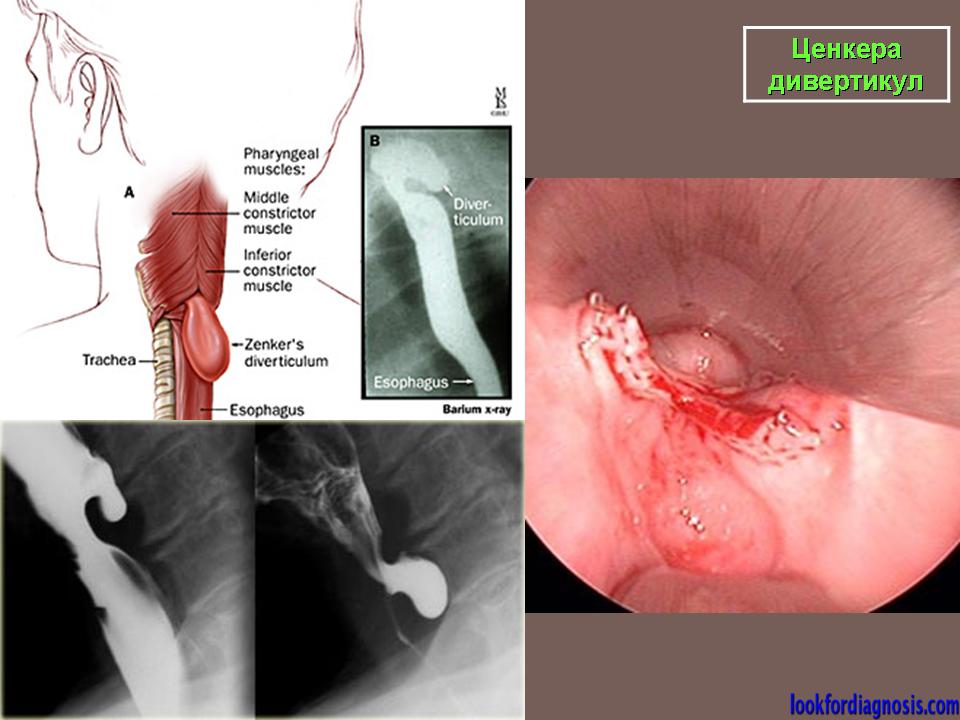

Ценкера дивертикул.

Barium swallow with fluoroscopy, lateral view</p> <p>During swallowing an outpouching of the posterior hypopharyngeal wall is clearly visualised at the level C5-C6, right above the upper oesophageal sphincter. The pouch is characterized by a narrow neck entrapping some barium after the swallowing.

ID: 12377 Zenker's diverticulum Dr Erik Ranschaert - 18 Nov 2010 Zenker's diverticulum

ID: 17006 Zenker's diverticulum Dr Roberto Schubert - 8 Mar 2012

Zenker's diverticulum AP </p> <p>

ID: 13718 Zenkers diverticulum Dr Lee-Anne Slater - 10 May 2011 Barium swallow showed a large posterolateral pouch just above the level ...

Дивертикул Ценкера.